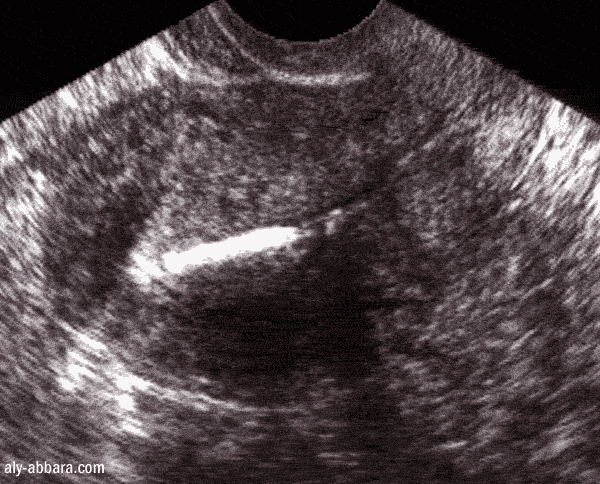

L'emplacement dans l'utérus vu par l'échographie

La branche verticale (la tige) du stérilet (coupe sagittale sur l'utérus)